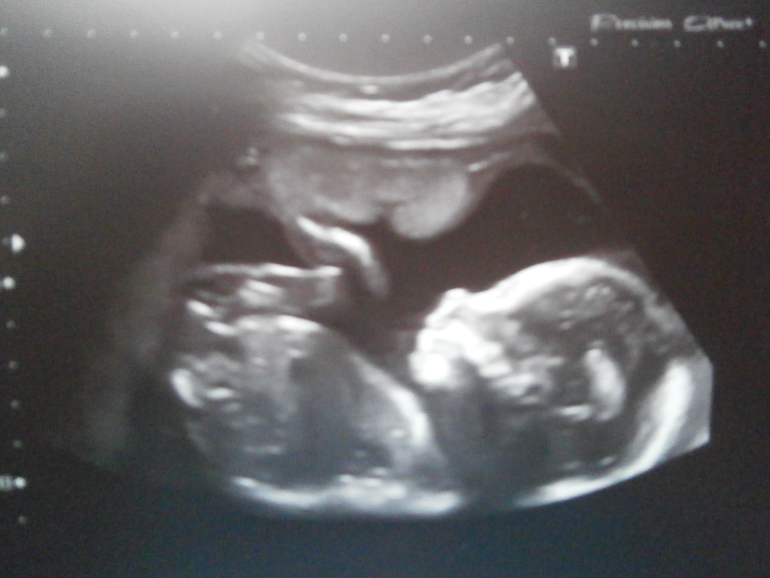

Были в 19 недель с мужем на узи: лежит наш пупсик с раздвинутыми ножками, врач сразу делает увеличенную фортку. улыбается и говорити "вот ваша плюшка". у нас будет дочурка как это классно

, мы с мужем смущенно переглянулись и начали слушать что у нашей принцессы все хорошо, все в норме

, весили на тот момент приблизительно 267 грамм .

А потом она начала переворачиваться, ручками лицо закрывать и толкаться. Пинается очень часто и когда находится в районе пупка, то даже иногда больно от пиночков.